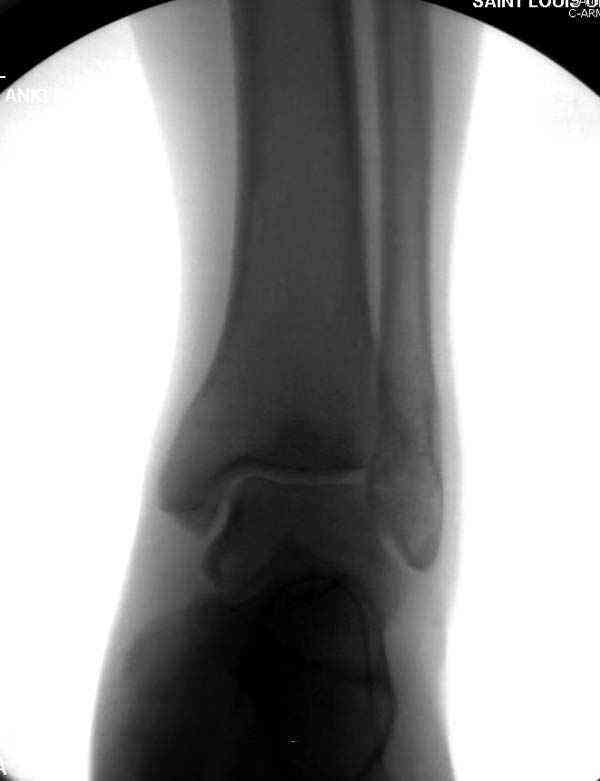

Раз ,есть желание посмотреть другую проекцию выкладываю-ну лучшего качества нет...

Кликните для загрузки файла DSC05256.JPG

2237KB (2290984 bytes)